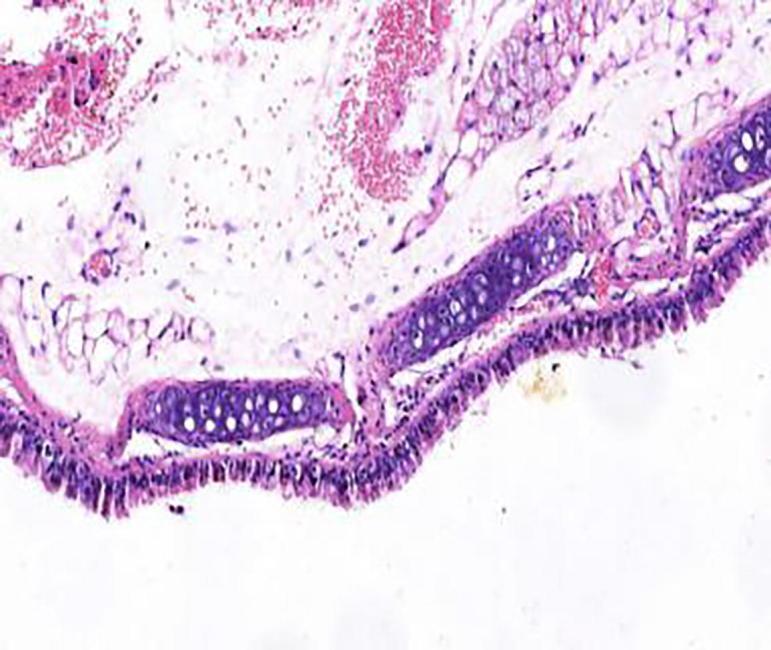

Compared with model group, the Schisandrae Fructus syrup groups can significantly increase the tidal volume of mice and decrease the respiratory frequency and the degree of bronchial stenosis ( < 0.01); The Schisandrae Fructus syrup groups can decrease the levels of NO and IL-6 in serum and improve the pathological changes of lung and bronchus in different degrees.

与模型组相比,五味子糖浆组可显著增加小鼠潮气量,降低呼吸频率及支气管狭窄程度(P<0.01);五味子糖浆组可降低血清中NO和IL-6水平,不同程度改善肺及支气管的病理变化。